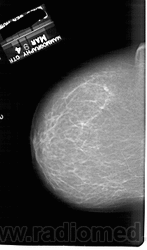

Жирная (не плотная) грудь

Умеренно плотная грудь

Плотная грудь

Маммограммы представляют собой изображения структур, проецируемых на плоскость: плотная грудная маммограмма, следовательно, состоит из многих других структур, которые необходимо проанализировать, чем более жирная, пустая грудь. По этой причине диагностировать рак молочной железы труднее для моложе, чем для пожилых женщин.

Нажмите на миниатюрные картинки, чтобы получить увеличенный размер.